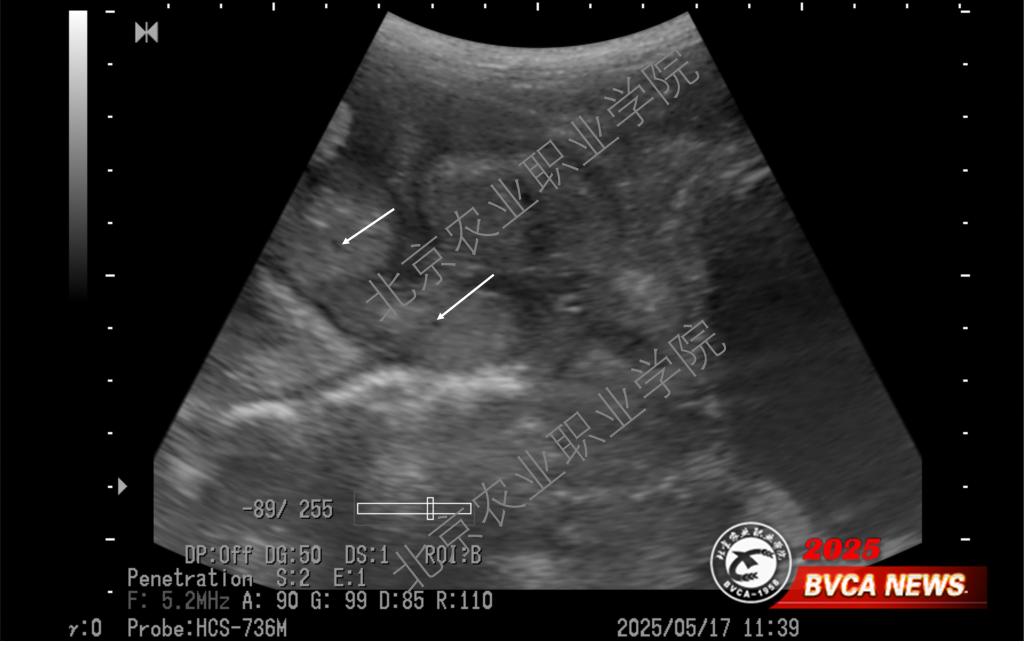

近日,受北京偉杰信生物科技有限公司邀請(qǐng),動(dòng)物科技學(xué)院獸醫(yī)超聲技術(shù)團(tuán)隊(duì)為該公司“母豬妊娠21天超聲檢查技術(shù)操作規(guī)范”項(xiàng)目提供了重要的技術(shù)支撐,并取得重大進(jìn)展。團(tuán)隊(duì)首席專家姜晨副教授梳理了母豬不同體位超聲掃查的方法,以便技術(shù)人員在不改變母豬體位的情況下做出準(zhǔn)確診斷,最大程度上降低懷孕母豬不必要的應(yīng)激。

近年來,我院姜晨副教授領(lǐng)銜的獸醫(yī)超聲技術(shù)團(tuán)隊(duì)積極推廣超聲影像技術(shù)在多種動(dòng)物臨床中的應(yīng)用,并取得一系列技術(shù)成果。團(tuán)隊(duì)持續(xù)探索母豬孕早期超聲檢查的邊界,目前最早可在排卵后第9天確認(rèn)是否懷孕(可見直徑約1mm的卵囊液)。此超聲檢查技術(shù)已達(dá)到國(guó)際前沿水平,為打開母豬孕初相關(guān)的科學(xué)研究之門提供了一把金鑰匙。